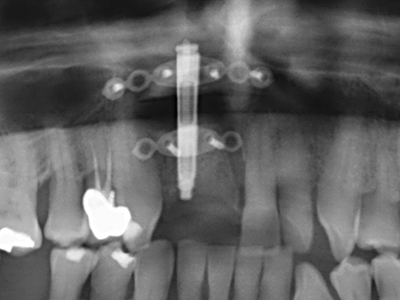

Si es preciso realizar intervenciones quirúrgicas en las que el hueso está en contacto directo con estructuras sensibles, como son los vasos sanguíneos o los nervios, los instrumentos rotativos presentan un enorme potencial de provocar lesiones iatrogénicas. Así, precisamente en la representación de nervios después de una lesión iatrogénica, o en el transcurso de la lateralización de un nervio para resecciones, reconstrucciones o incorporación de implantes, los equipos piezoeléctricos pueden resultar muy útiles para preparar la tapa ósea y retirar las partes de tejido duro cercanas al nervio (fig. 17-20). Por lo general, un ligero contacto del cordón nervioso con el inserto piezoeléctrico no tiene consecuencia alguna; ahora bien, un procedimiento poco cuidadoso con movimientos tipo sierra o piezas de trabajo sobre la base ósea aún existente puede provocar lesiones nerviosas temporales o incluso permanentes. Con todo, el riesgo de sufrir una lesión de este tipo se considera significativamente inferior que en los casos en los que se utilizan sierras y fresas (Pereira, Gealh et al. 2014).

Como ya se ha demostrado en el pasado, básicamente cualquier procedimiento de cirugía de hueso representa una posible indicación para la cirugía piezoeléctrica. Así, la preparación del segmento móvil en la osteogénesis de distracción (fig. 23-25) y en la osteotomía de sándwich puede realizarse con piezas especiales, sin poner en peligro el suministro sanguíneo de la parte crestal, que resulta esencial para el éxito de ambas técnicas (González-García, Diniz-Freitas et al. 2008).

Para la extracción de implantes es posible realizar la preparación de una tapa ósea vestibular que, tras retirar el tornillo del implante, vuelve a fijarse y, de este modo, mantiene el contorno de la apófisis alveolar.

En la cirugía del seno maxilar surgen otros campos de aplicación: En este punto, tras la preparación concéntrica de una tapa ósea de la pared del seno maxilar (que suele tener forma trapezoidal), es posible eliminar patologías y cuerpos extraños del seno maxilar. La tapa ósea se repone después de finalizar la parte intra-antral de la operación y se asegura frente a una posible dislocación mediante cuñas o suturas adaptables.